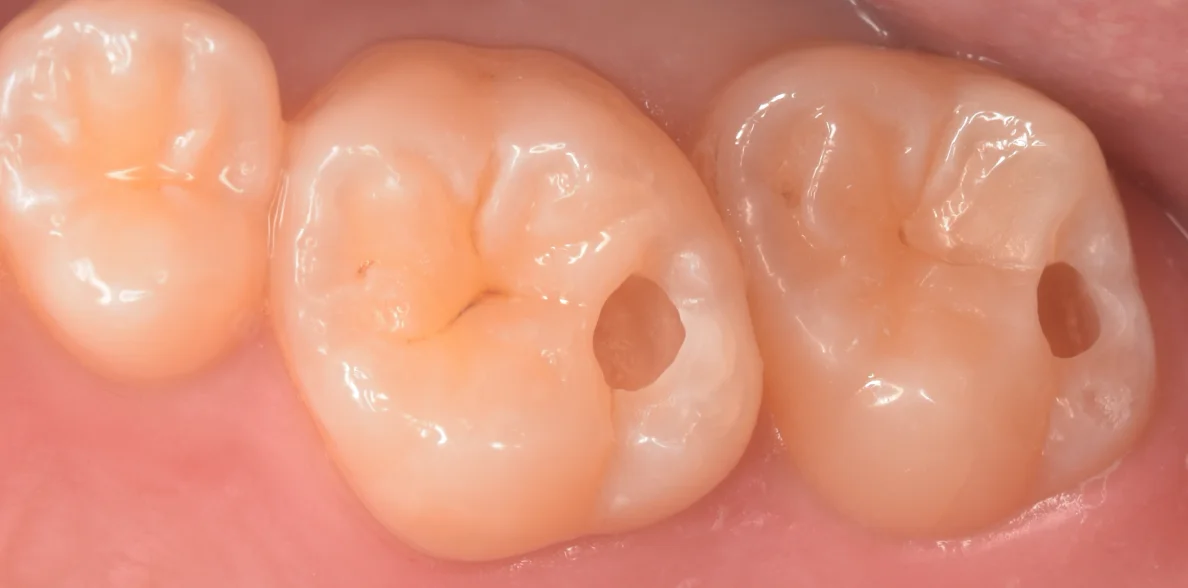

そして治療終了後の写真がこちらになります。

ギャップもなく、違和感のない形態が付与できたと思います。

色については1週間くらいすると歯の表面のエナメル質に水分が戻り、馴染んできますのでご安心ください。

では術前術後の写真です。